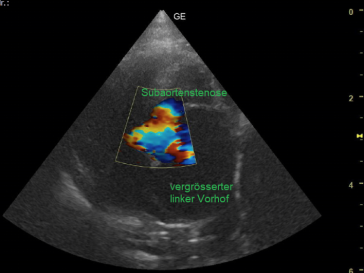

Mit dem Ultraschall werden der Herzmuskel und seine Anhänge dargestellt. Die verdickten Klappenteile, das Ausmass des Pendelblutes, der vergrösserte Vorhof und Ventrikel sowie die Druckdifferenzen sind mess- und darstellbar. Nach dieser systematischen Erfassung und Beschreibung beurteilt die Tierärztin den Schweregrad der Erkrankung und definiert Therapie-Optionen.

Ausmass des Pendelblutes in den linken Vorhof in Farben.

Farb-Doppler Darstellungen

dynamische subaorta- und midventrikuläre Obstruktionen führen zum links-Herzversagen

durch Rückfluss hochgradig vergrösserter Vorhof: Aorta/linkem Vorhof > 1.5